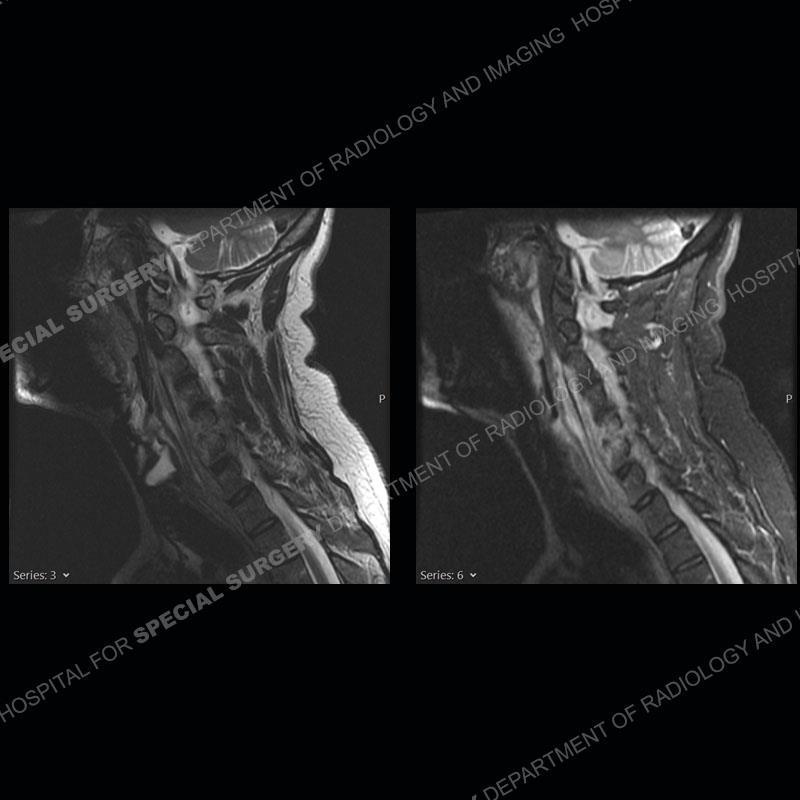

The radiographs demonstrate a prevertebral soft tissue fullness centered at C5-C6 that persists even on extension. There is a slight loss of disc height at C5-C6. The CT more readily shows the prevertebral soft tissue swelling at C5C6 where there is a punctate focus of gas. On the MRI, there is a marked amount of edema and a heterogeneous collection in the prevertebral soft tissue at C5-C6. Edema is present of the C5 and C6 vertebral bodies with a loss of the normal architecture about the disc space. A heterogeneous epidural collection has formed that causes compression of the spinal cord asymmetric to the left side and also precipitates severe left sided neural foraminal stenosis.